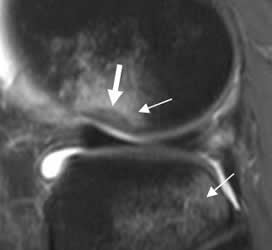

Fig 29. Contusión ósea.

RM sagital en STIR. Clásica contusión del platillo tibial y cóndilo femoral lateral, con signo de la muesca, encontrado en rupturas del LCA.